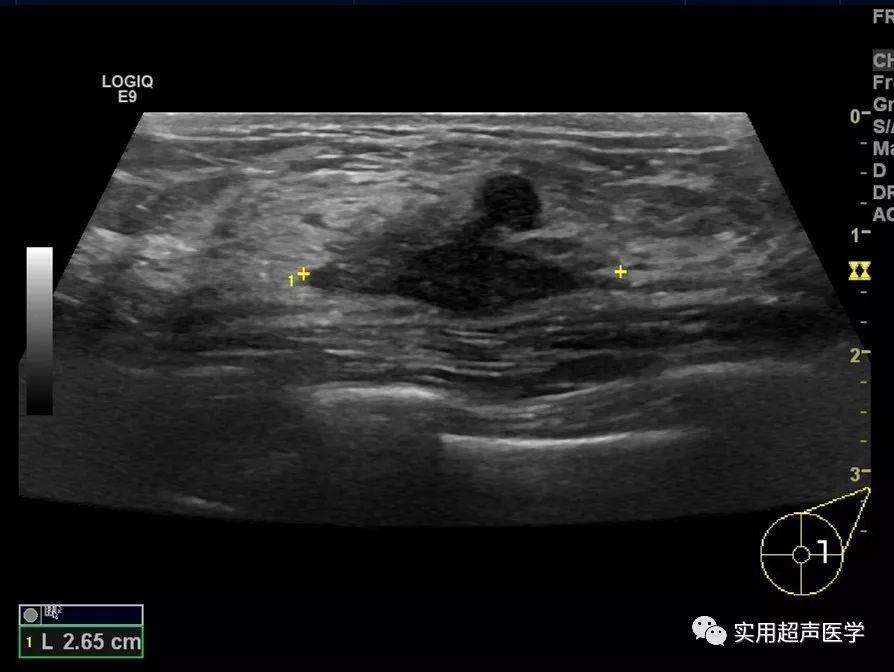

女性,34 岁,左侧乳腺扪及无痛性硬块。

超声检查为不规则的非均质低回声肿块。

肉芽肿性乳腺炎超声表现与乳腺癌相似,表现为单个或多个不规则形低回声区,形状不规则,内回声不均匀,CDFI显示低回声边缘及内部可见丰富血流。部分低回声潜行至皮下形成皮下及皮肤病灶。